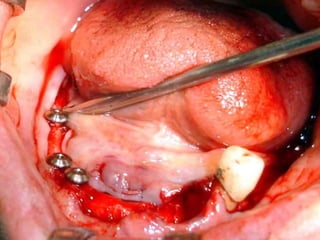

Segundo tiempo quirúrgico para aplicar la estructura.

Estructura en íntimo contacto con la superficie ósea, quedando los postes

fuera de la fibromucosa gingival..

Sutura de colgajos que cubren la estructura, dejando los postes bien visibles.

Colocación de la prótesis dentaria.

Estructuras metálicas subperiósticas:

Tornillos para fijación en hueso:

Prótesis:

Segundo tiempo quirúrgico:

Estructura implantada por debajo del periostio:

• Los implantes subperiósticos son parte de la historia de la

Odontología, sin embargo en su momento fueron una buena